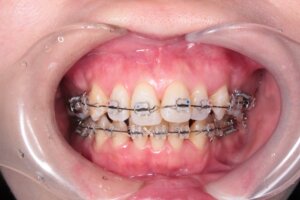

抜歯をしたスペースに歯を移動させることによって自然と前歯の重なりがほどけてきました。

そして、ついに前歯にもブラケットを付けることが出来るようになりました。

すでに正面から見た印象が大きく変わりました。